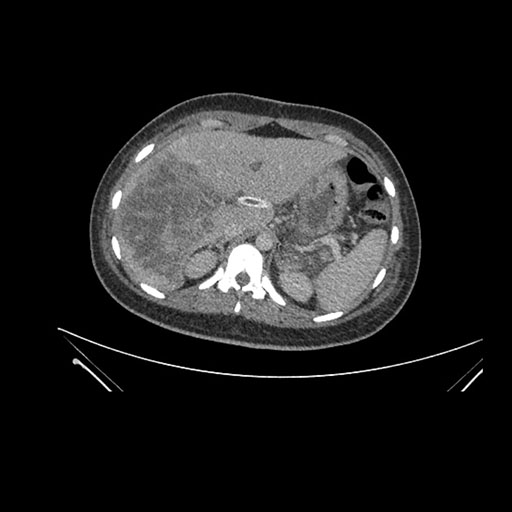

Axial Arterial

Axial Venous